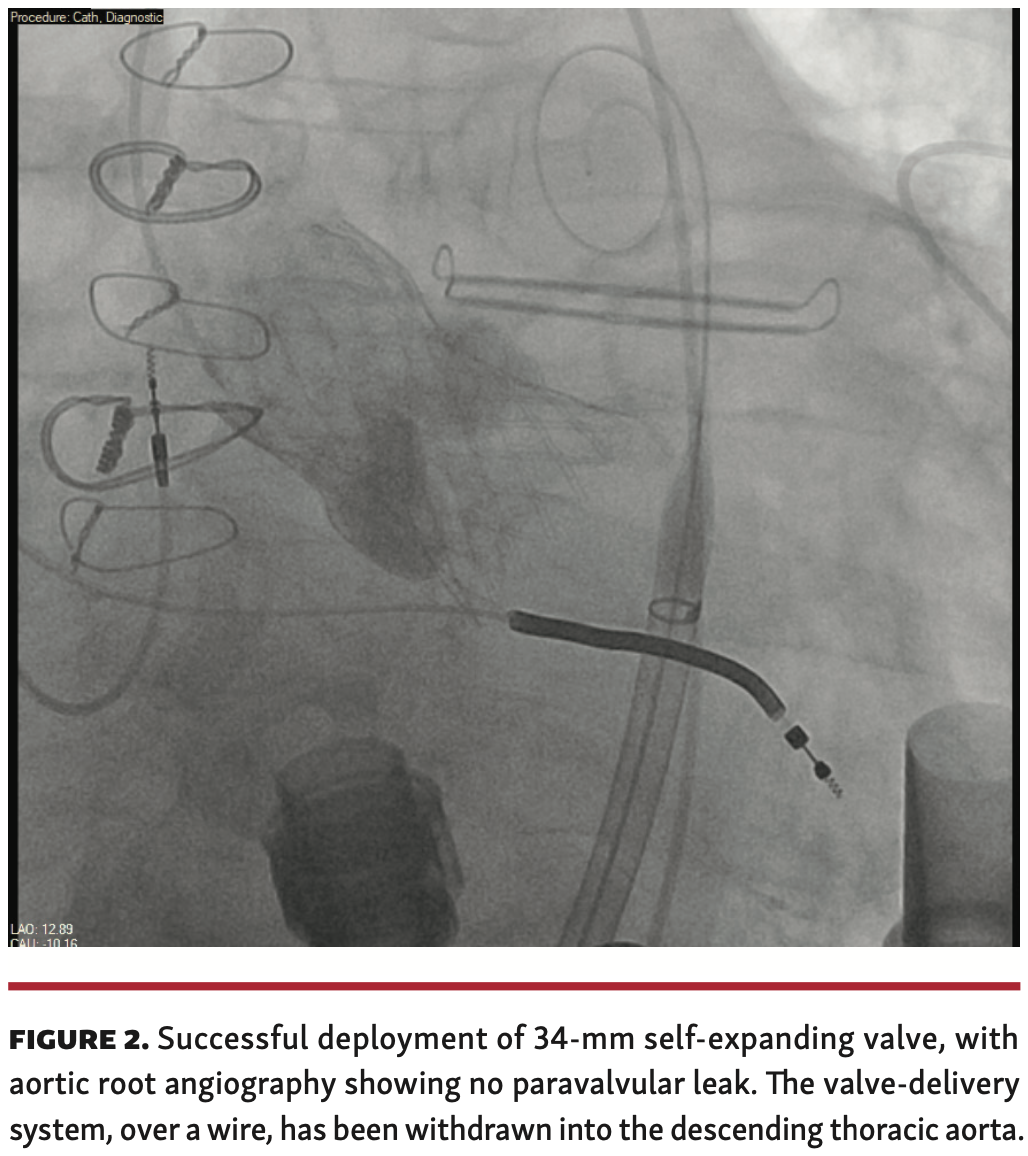

Procedural technique. A 34-mm Evolute SEV (Medtronic) is advanced over a double-curve Lunderquist wire (Cook Medical) and positioned within the aortic annulus. Aortic root injections are performed. Without pacing, the valve is slowly deployed to 80% with repeated aortic root injections and transthoracic echocardiographic evaluation. The valve is observed in this position for 5-10 minutes to see if it appears to be migrating into the left ventricle. The LVAD flow rate is slowed and with rapid pacing the valve is then released (Figure 1 and Figure 2). Rapid pacing is discontinued. Over 5-10 minutes, the LVAD flow rate is ramped up to baseline rotations/minute with continuous observation under echocardiography and cine angiography. Procedural variables are listed in Table 2. All 4 of our patients underwent TAVR with a 34-mm Evolut SEV (Medtronic). For patient 4, who developed moderate paravalvular leak (PVL) with ventricular migration of the SEV, we deployed a 29-mm Sapien 3 BEV (Edwards Lifesciences) within the SEV, with fluoroscopically visible expansion of the “waist” of the SEV (Figure 3 and Figure 4).